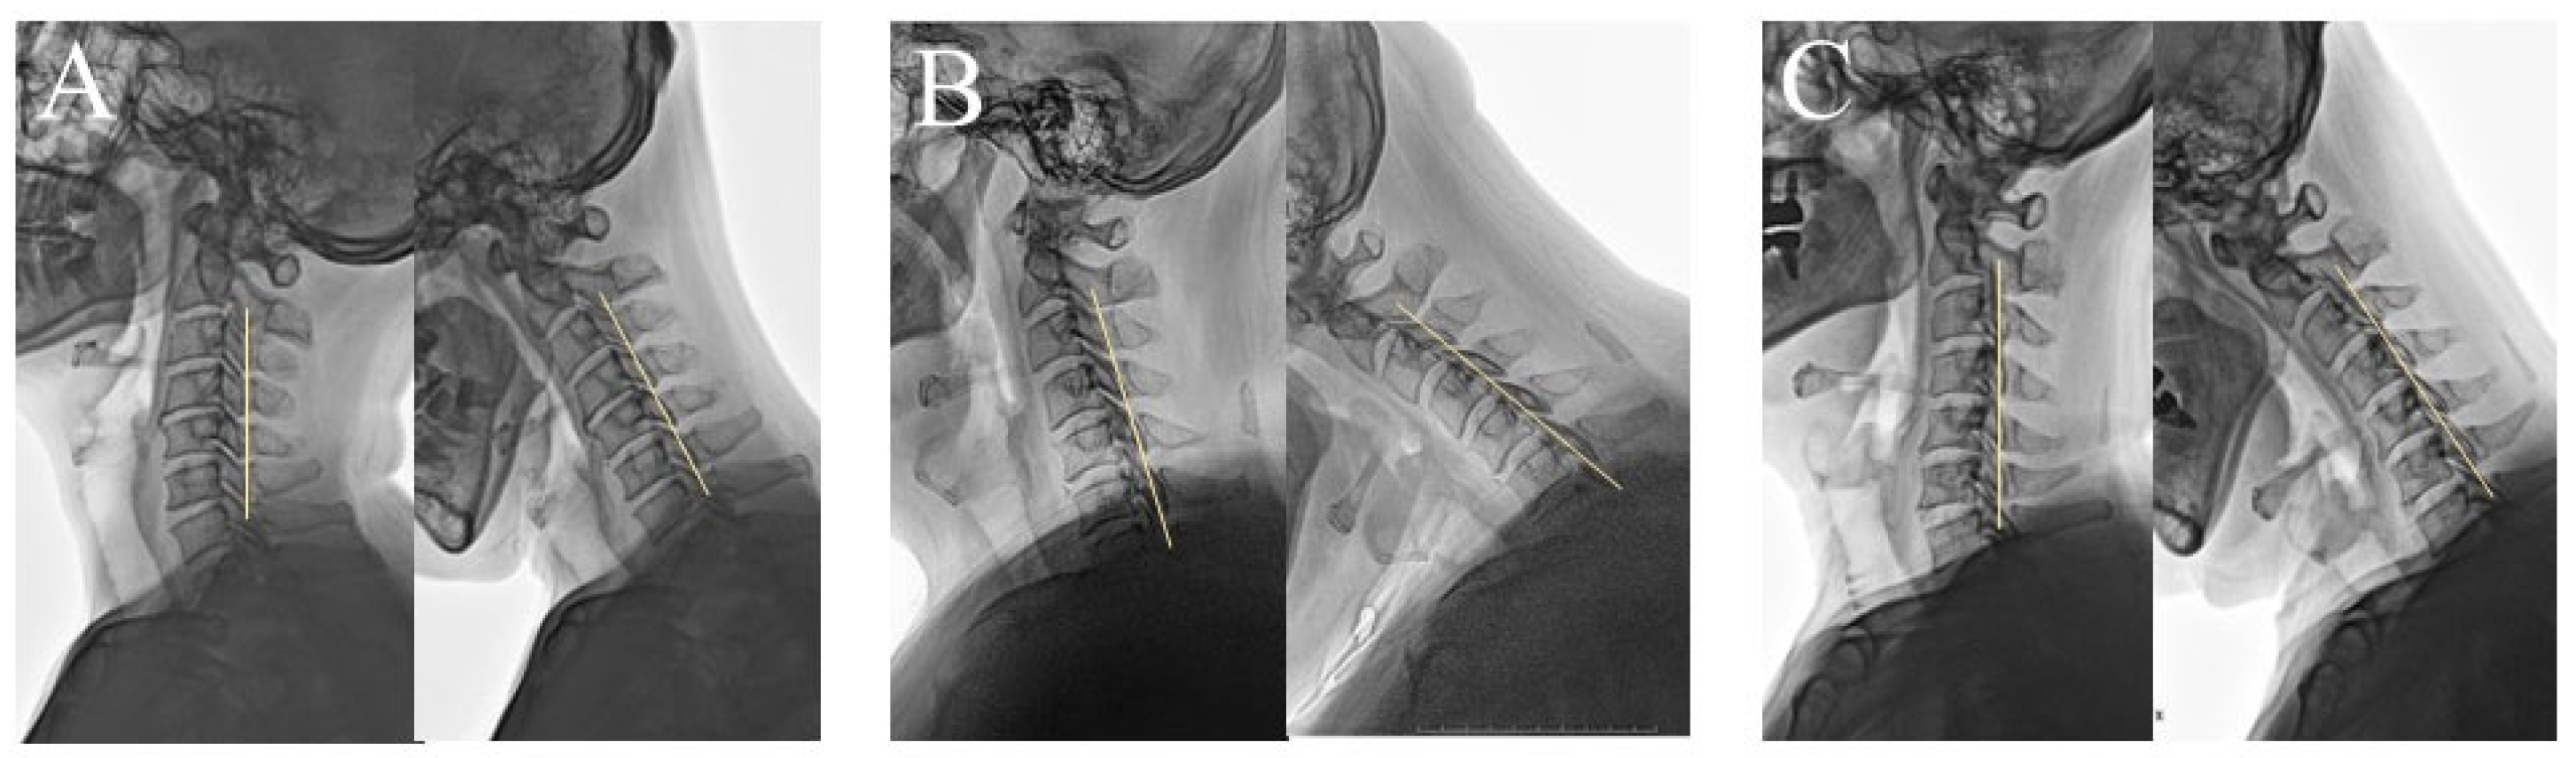

2.1. Radiologic Evaluation